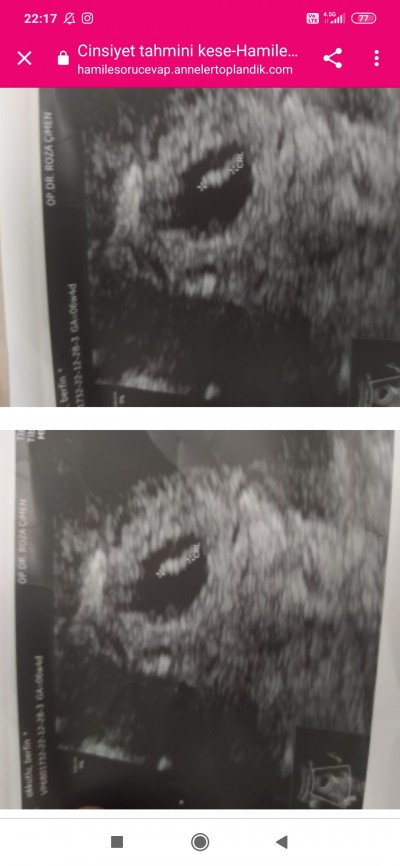

6+4kalp atisini dinledik keseye göre cinsiyet tahmini diye bisey var dogrumu

Gebelik haftası 8+2